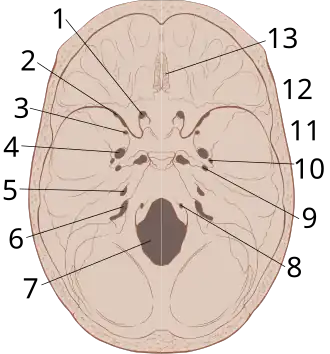

Epidural hematomas usually appear convex in shape because their expansion stops at the skull's sutures, where the dura mater is tightly attached to the skull. Thus, they expand inward toward the brain rather than along the inside of the skull, as occurs in subdural hematomas. Most people also have a skull fracture.[3]

A diagram showing an epidural hematoma.